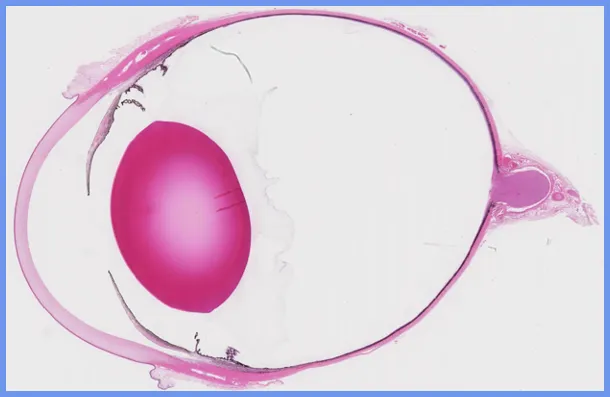

Corneal Ulceration and Keratitis

We will review the typical responses of the cornea to ulceration and some of the main patterns of keratitis.